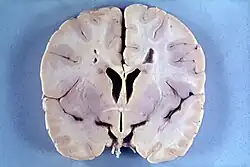

Many people with abnormally large heads or large skulls are healthy, but macrocephaly may be pathological. Pathologic macrocephaly may be due to megalencephaly (enlarged brain), hydrocephalus (abnormally increased cerebrospinal fluid), cranial hyperostosis (bone overgrowth), and other conditions. Pathologic macrocephaly is called "syndromic", when it is associated with any other noteworthy condition, and "nonsyndromic" otherwise. Pathologic macrocephaly may be caused by congenital anatomic abnormalities, genetic conditions, or by environmental events.[2]